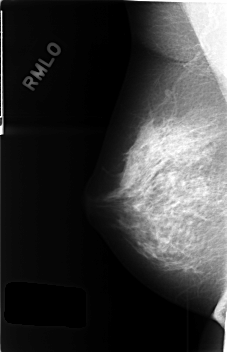

C_0434_1.RIGHT_MLO

RIGHT_MLO LINES 4568 PIXELS_PER_LINE 2944 BITS_PER_PIXEL 12 RESOLUTION 50 NON_OVERLAY